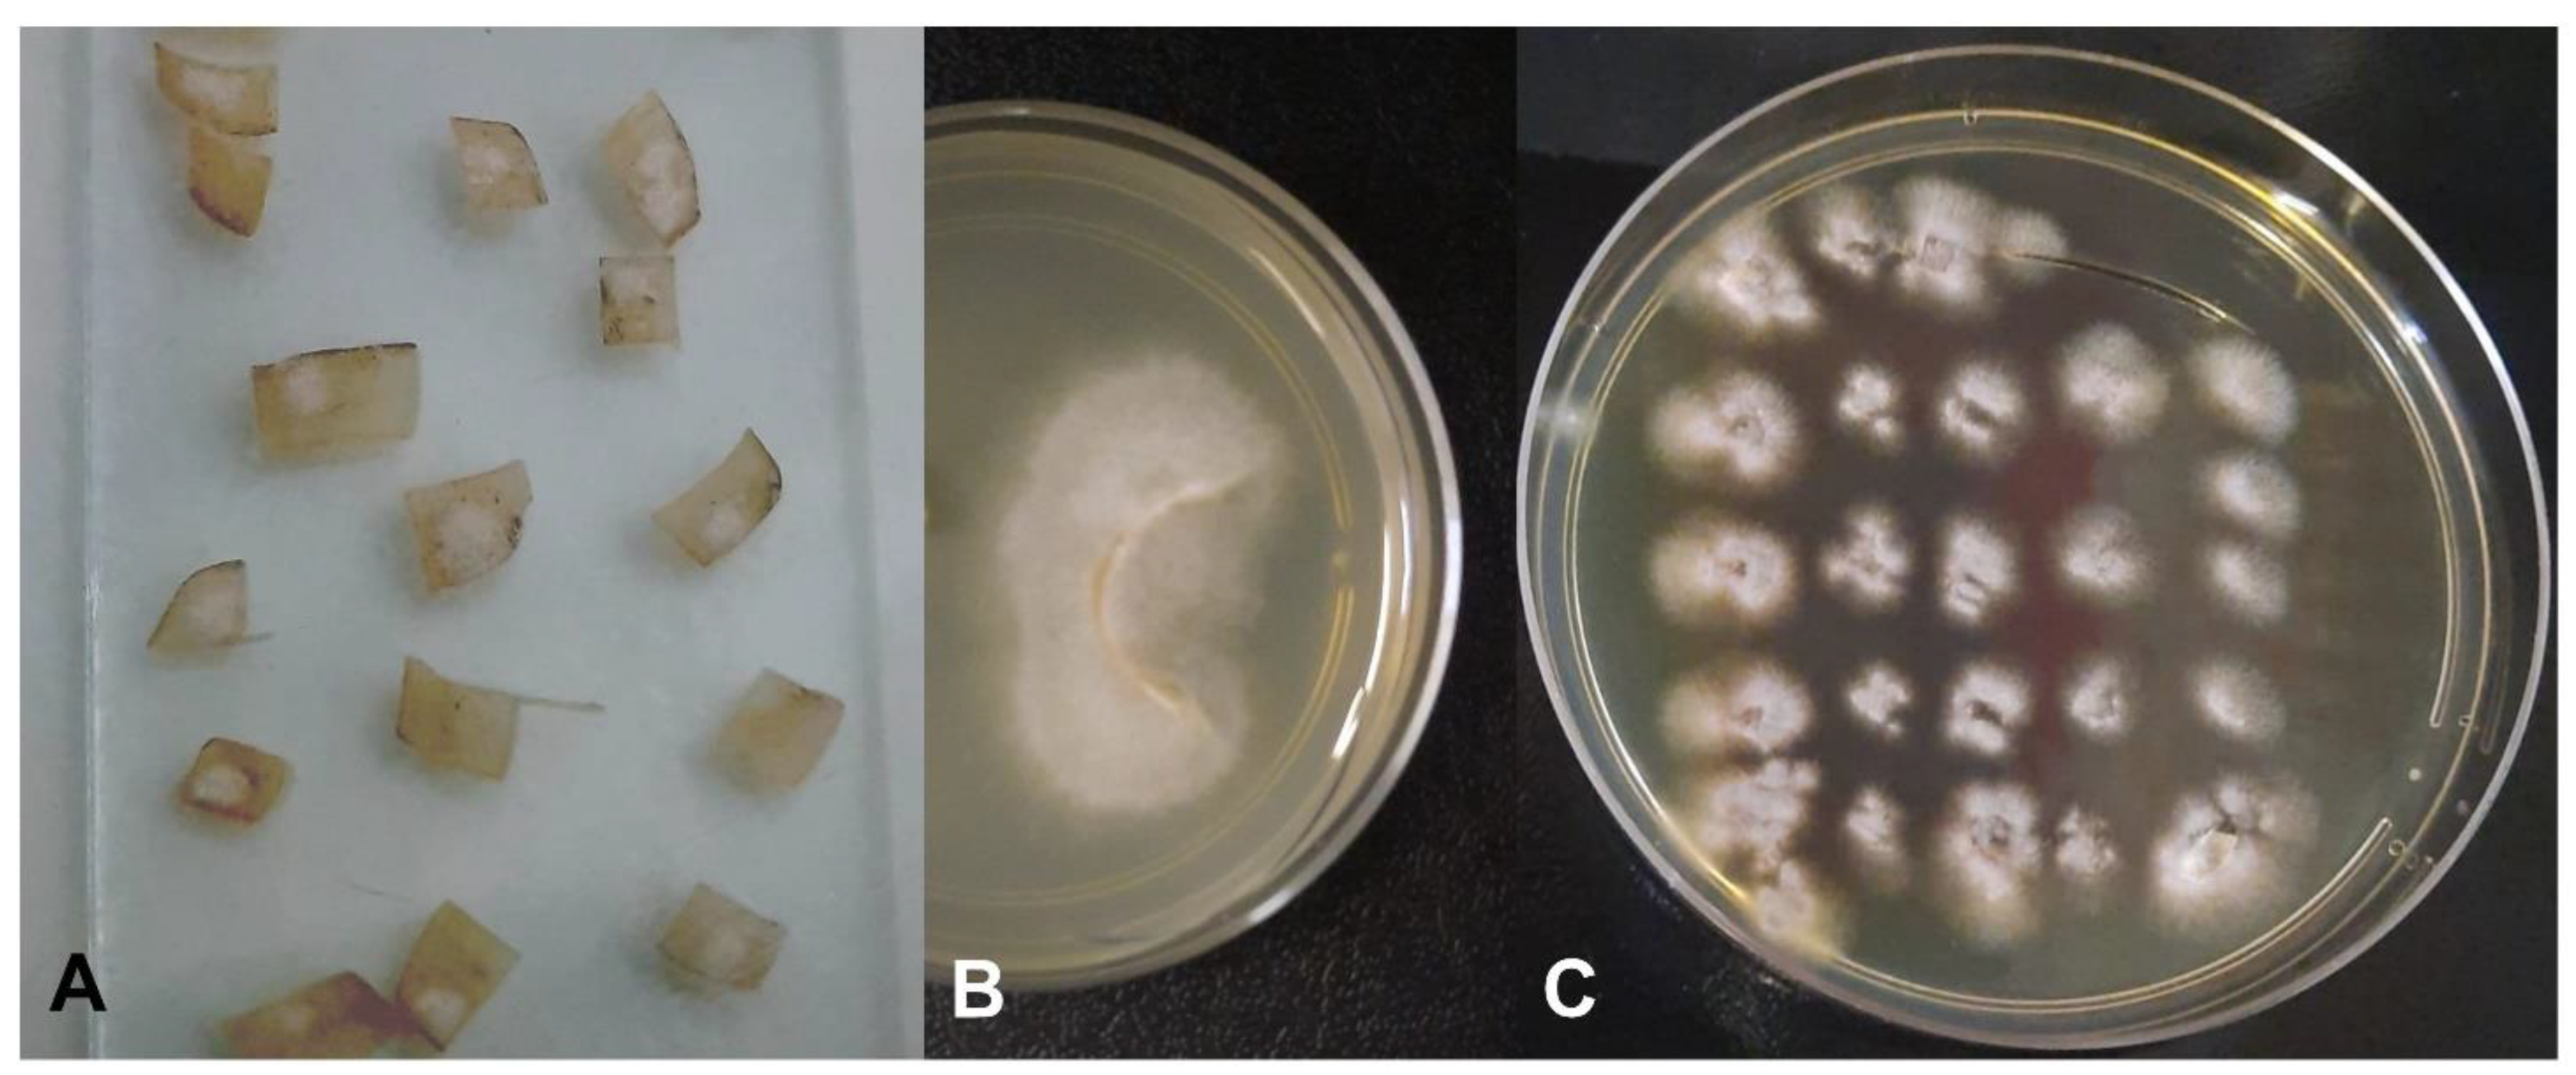

2.3. Characterization of Fungal Growth and Biofilm Formation of the Clinical Isolate in an Ex Vivo Model

2.4. In Vitro Effects of Propolis on the Isolated Fungus